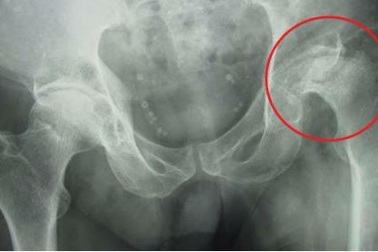

Phát hiện hoại tử chỏm xương đùi độ IV do đau háng đột ngộtNgay sau khi phát hiện tình trạng hoại tử chỏm xương đùi độ IV, bệnh nhân N.V.T (54 tuổi) đã được phẫu thuật thay khớp háng thành công bằng kỹ thuật SuperPATH hiện đại tại BVĐK Hồng Ngọc.

Căn bệnh ngày càng trẻ hóa gây tàn phế, tấn công người lạm dụng rượu biaBác sĩ cảnh báo, tình trạng này thường gặp ở độ tuổi 20-50 và ngày càng trẻ hóa, gây gãy xương, mất chức năng khớp háng dẫn đến tàn phế. Người lạm dụng rượu bia là đối tượng nguy cơ mắc bệnh.